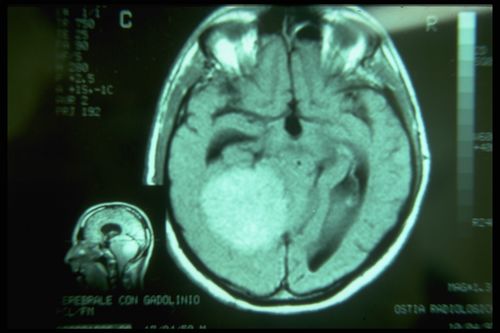

Nel nostro laboratorio di neurofisiologia masticatoria abbiamo messo a punto una tecnica di elettrostimolazione trasncraniale elettrica delle due radici trigeminali in simultanea e sincronizzate con lo stimolo elettrico. Nei vari capitoli già pubblicati sono riportati alcune informazioni tecniche sul metodo ma ci ripromettiamo di esporli in modo esaustivo nella sezione 'Scienza straordinaria' Un questa sede possiamo solo considerare e confermare una asimmetria notevole di ampiezza delle risposte evocate motorie come mostrato in figura 3. I markers 1A e 2A indicano la latenza che a differenza del periodo silente è simmetrica e questo dato conferma che il danno strutturale riguarda le fibre sensitive comprese quelle propriocettive dai muscoli masticatori. Possiamo a questo punto non solo confermare e giustificare la scelta neurologica del contesto diagnostico ma anche concludere con una pre diagnosi di danno neurologico cerebellare con coinvolgimento dell'area mesencefalica trigeminale. Contestualmente interrompiamo il riciclarsi dell'intervento riabilitativo protesico per indirizzare il paziente immediatamente al reparto radiologico per una Risonanza Magnetica dell'encefalo.

lesione espansiva solida con effetto massa, non è chiaro se abbia un’origine sopra o sotto tentoriale, sicuramente determina fenomeni compressivi sul mesencefalo - tronco e probabilmente sul quarto ventricolo con dilatazione delle cisterne e dei ventricoli a monte. Che si tratti di un meningioma è molto probabile perché non ha edema perilesionale.

Figura 4: